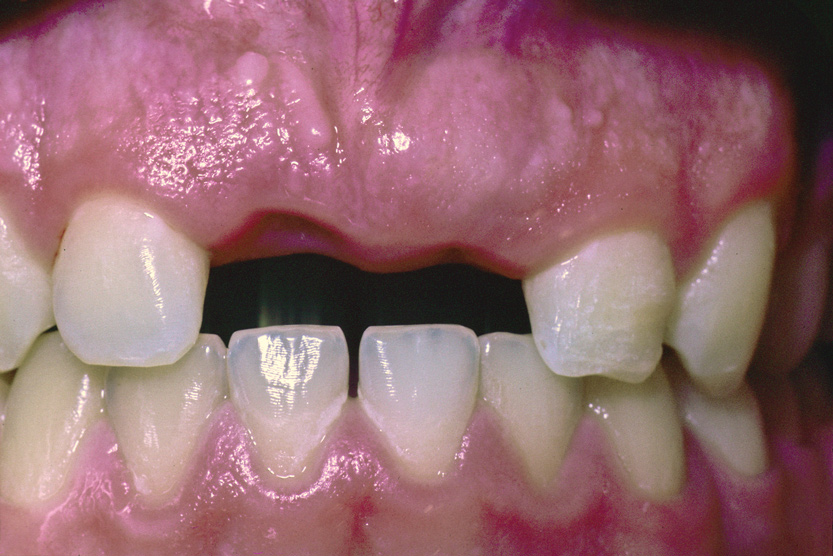

A healthy 9-year-old boy was referred for evaluation and treatment of his maxillary central incisors. He had been in a bicycle accident 2 weeks earlier. The right central incisor had been avulsed and the left central incisor had a class II fracture of the mesioincisal edge. Tooth No. 8 had been replanted after 90 minutes, and orthodontic brackets were placed to splint and position the tooth in anticipation of ankylosis.

Teeth Nos. 7 through 10 were included in the endodontic examination. Nos. 7 and 10 responded to cold; there was no response to cold or electric pulp test (EPT) from either tooth No. 8 or 9. All the teeth gave a mild positive response to percussion, and none of the teeth were tender to palpation. Both Nos. 8 and 9 probed within normal limits (WNL). Radiographs showed a small apical radiolucency associated with No. 8 and a widened periodontal ligament (PDL) on the mesial and apical aspect of No. 9 (Figure 12). An access was made in No. 8, and the canal was debrided and filled with Ca(OH)2.

Fig 12. Age 9. Radiograph of teeth Nos. 8 and 9 at initial examination. Orthodontic brackets were placed to stabilize the teeth.

Figure 12

Fig 13. Age 9. Obturation of teeth Nos. 8 and 9.

Figure 13